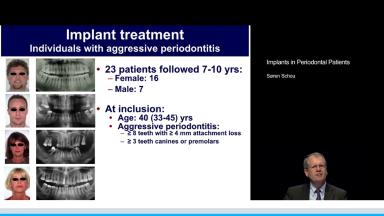

This lecture presents an overview of factors important to achieve predictable long-term results with implant therapy in patients with aggressive periodontitis and is based on a study of 23 patients followed for 7 to 10 years. The importance of preoperative infection control is underlined, with the aim to achieve absence of residual pockets of ≥ 5 mm with bleeding on probing, full-mouth plaque score < 20%, and the extraction of non-retainable teeth. The complexity of treating these patients is often increased by the indication of staged and/or simultaneous bone grafting procedures. By adhering to a strict preoperative infection control and meticulous treatment planning, a high implant survival rate of 98% was achieved after 7 to 10 years.